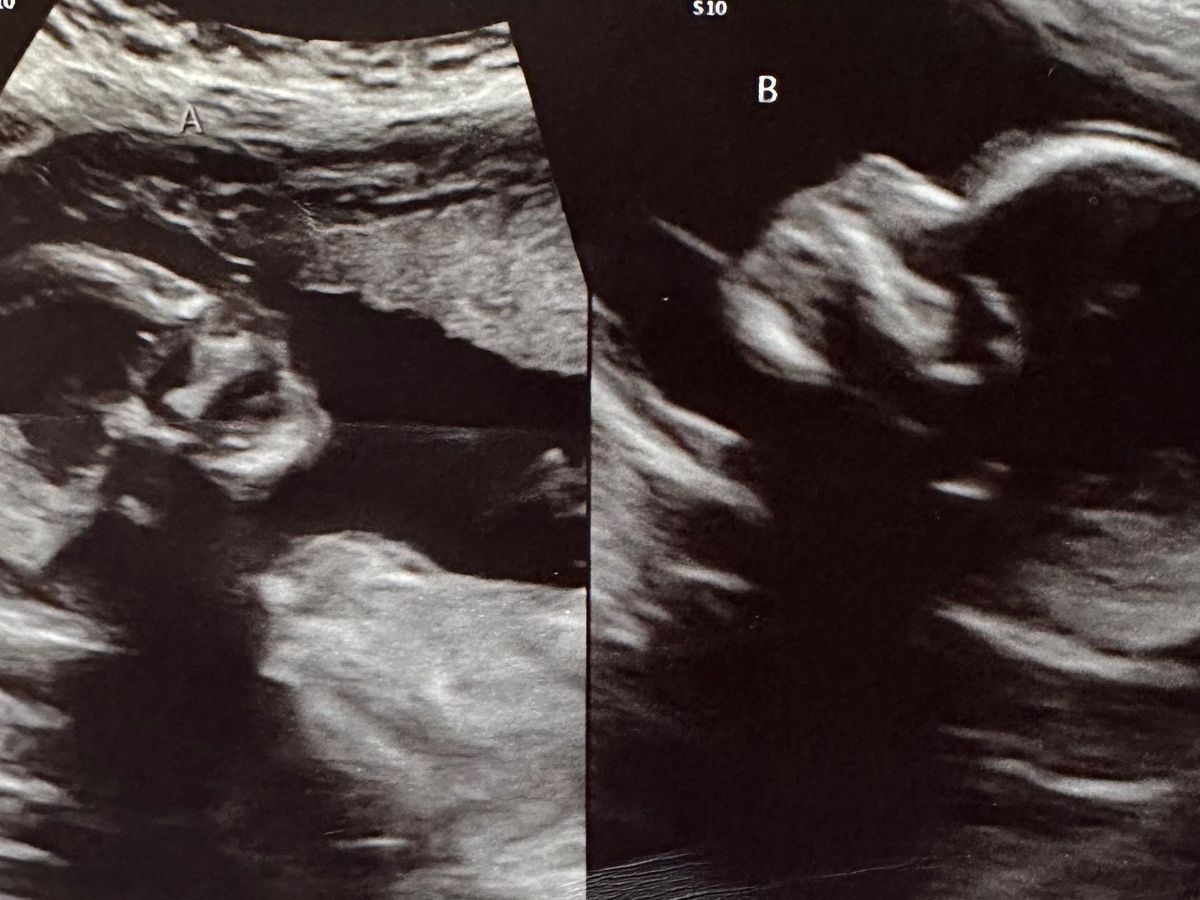

Caleb and Kelsey are currently pregnant with twins, with a 1 in 50 million chances pregnancy! Kelsey has a didelphic uterus, two separate uteri and two cervices, with a baby in each.